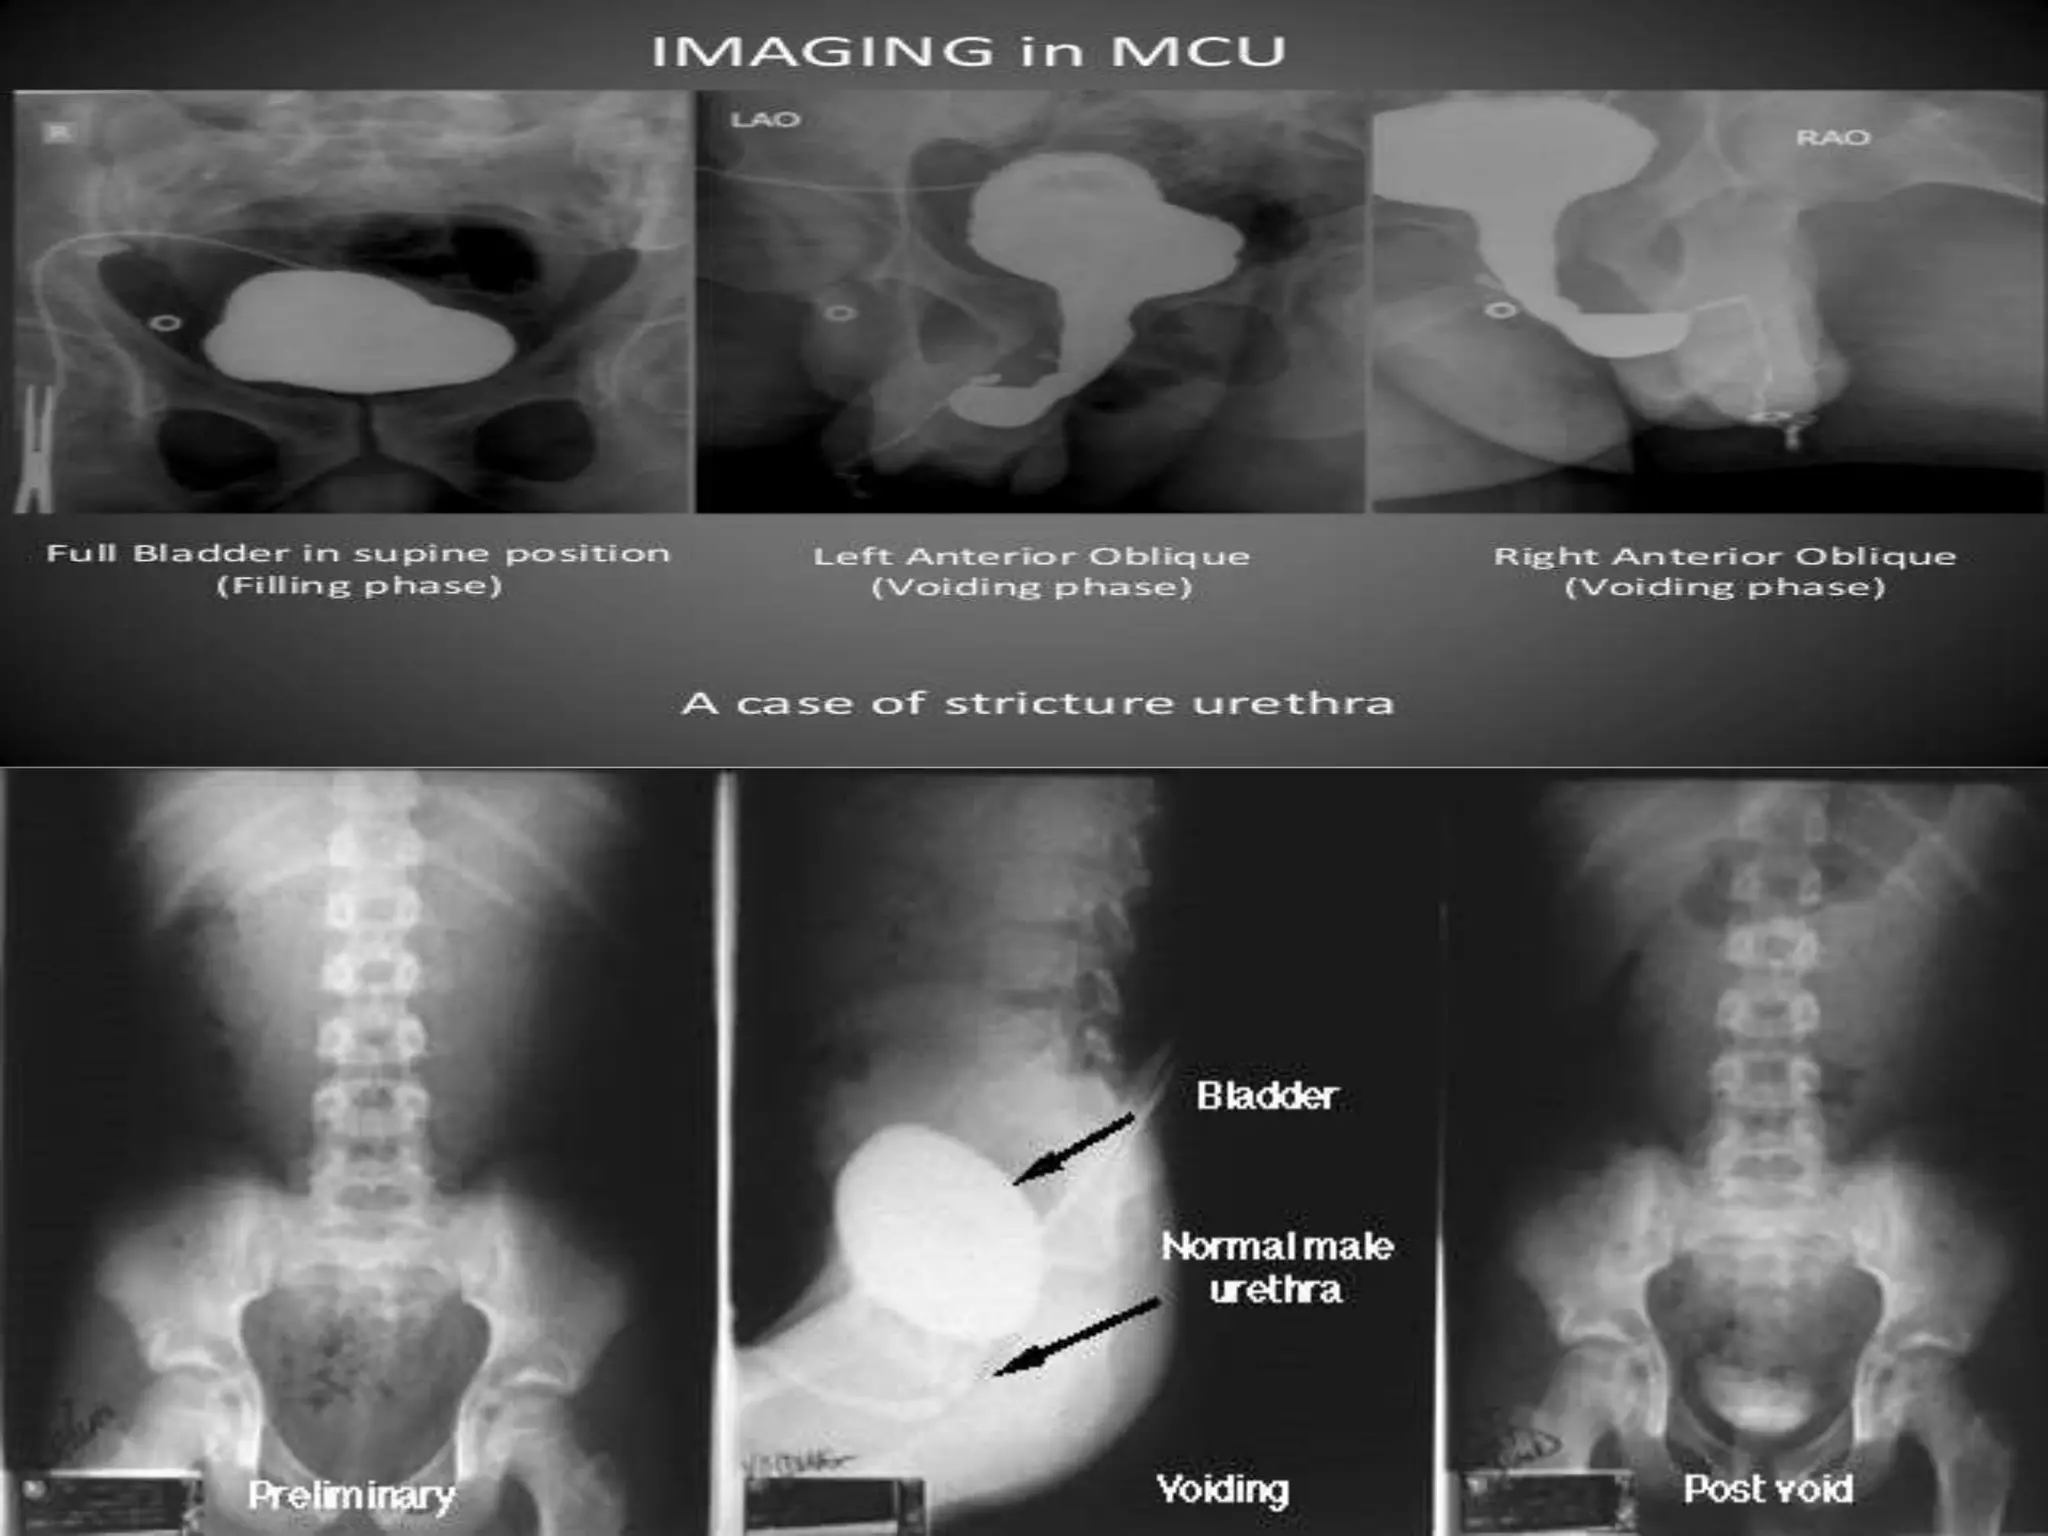

 The view of films:

30 left anterior oblique with right leg abducted and knee

flexed

Supine PA

30 right anterior oblique with left leg abducted and knee

Imaging  The viewof films: 30 left anterior oblique with right leg abducted and knee flexed Supine PA 30 right anterior oblique with left leg abducted and knee flexed